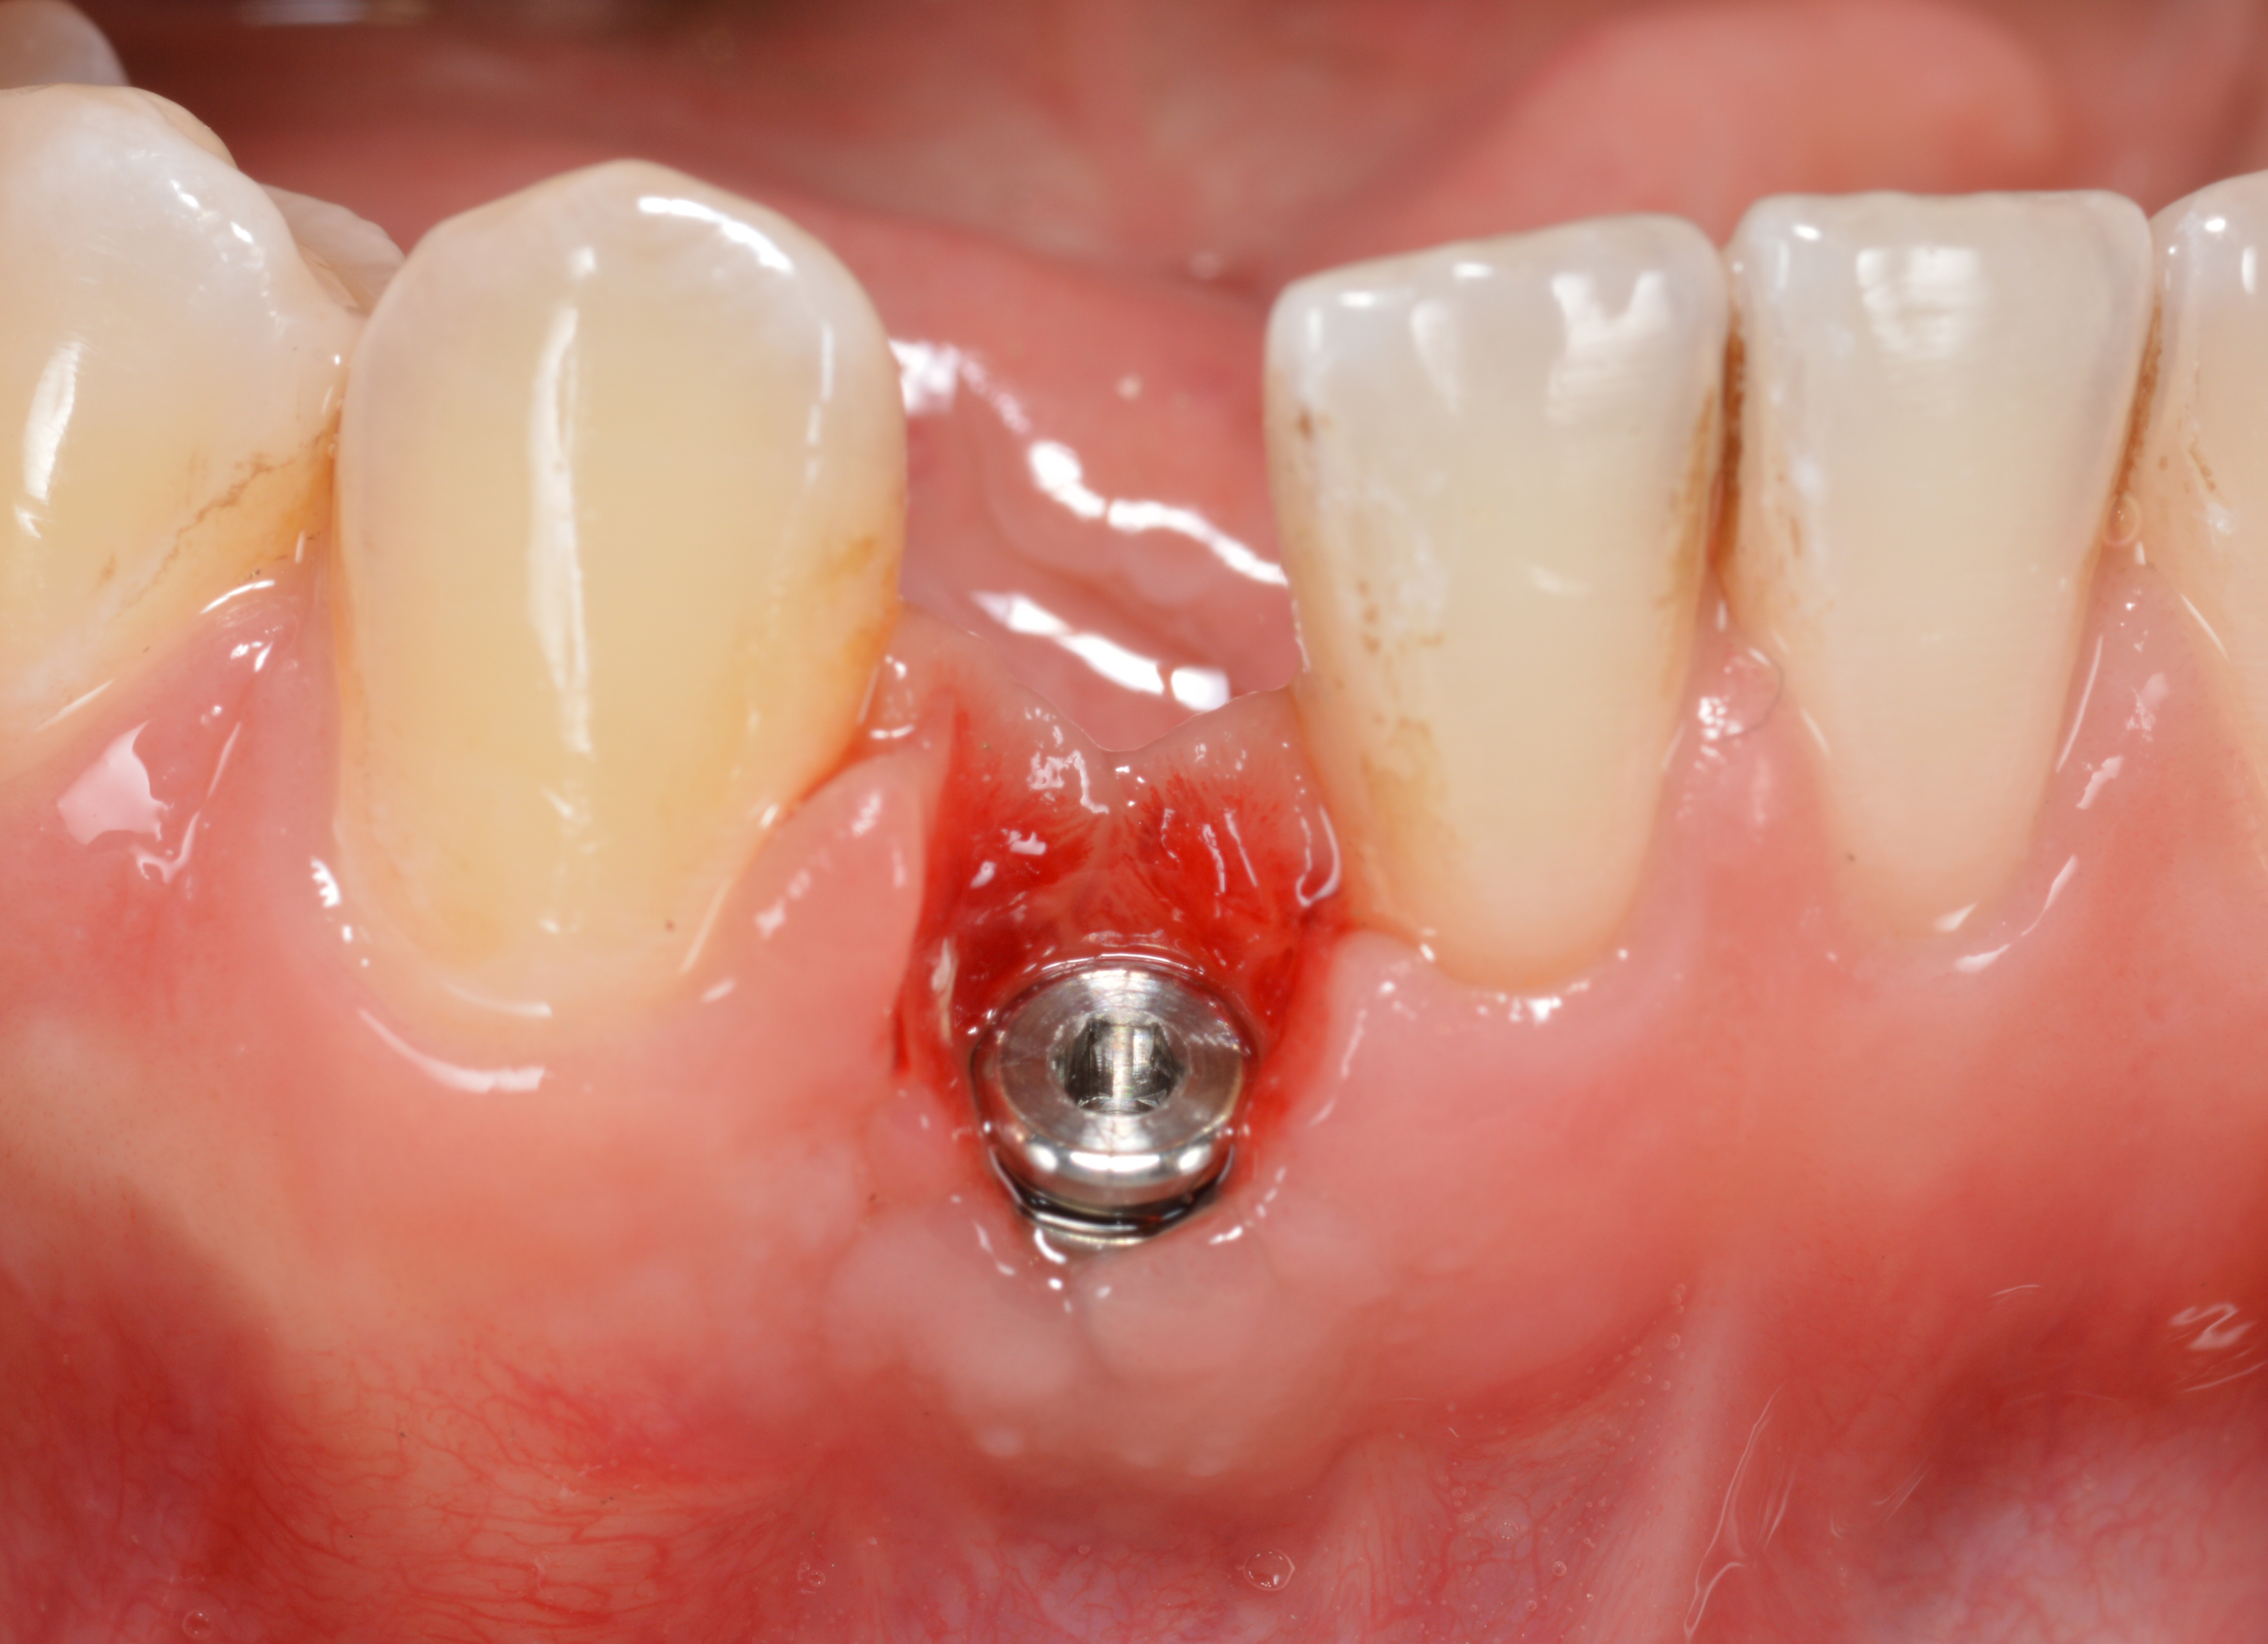

The crown and screw-retained custom abutment were removed, and a surgical cover screw was placed into the implant, thereby allowing spontaneous gingival augmentation in situ (Figure 33 and Figure 34). Note that the lingual aspect of the implant site was significantly more coronal than the labial aspect, which was positive because the defect would be limited to a facial–lingual defect. A fixed RBR bridge was cemented on the adjacent teeth and used as a tooth-supported transitional provisional restoration (Figure 35). A few weeks were allotted to let the soft tissue heal and migrate around the cover screw (Figure 36) to see if there would be complete coverage, thereby allowing a soft-tissue augmentation procedure to be performed with primary flap closure as in clinical scenario No. 2. The major obstacle in achieving a positive tissue response was that the implant depth was also deficient because the implant–abutment connection was at the level of the free gingival margin. It was decided that the best treatment option would be to remove the implant. A high-powered reverse-torque device (Fixture Remover Kit, NeoBiotech, www.neobiotechus.com) was used to remove the implant atraumatically (Figure 38 through Figure 41). The implant socket was allowed to heal for several months not unlike an extracted tooth (Figure 42). A new implant was placed in a better position from both a restorative and esthetic perspective (Figure 43), and after a few months of healing, a new crown was made (Figure 44). A satisfactory functional and esthetic result was achieved (Figure 45 and Figure 46) without employing pink porcelain.

Fig 34. A surgical cover screw was placed in an attempt to decoronate the implant and gain soft-tissue coverage in situ.

Fig 36. Two weeks after RBR placement, the soft tissue did not adequately cover the implant. The problem was in poor implant angulation and proper depth to allow the soft tissues to cover over.